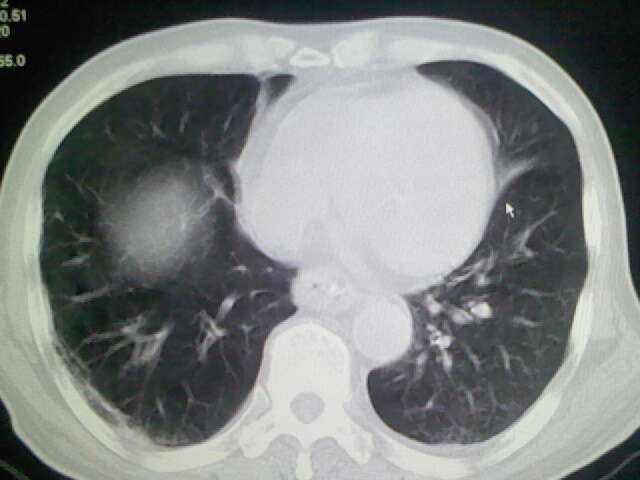

右肺病灶考虑炎症性。

右肺病灶考虑炎症性

考虑右肺及左肺下叶炎症。

右肺及左肺下叶炎症。

考虑右肺及左肺下叶慢性炎症。

右侧肺部见片状密度增高影,边缘模糊。考虑炎症。另食管壁增厚。

右肺肺气肿并炎症。

右肺上叶前段病呈楔形,其尖端指向肺门,考虑肺动脉栓塞可能性大.